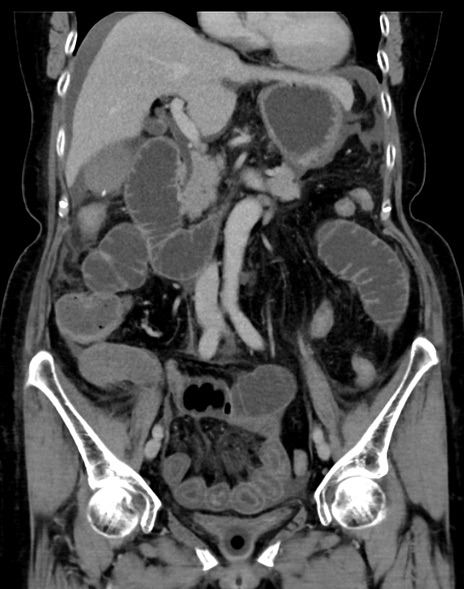

症例13 CT(冠状断像)1日半後